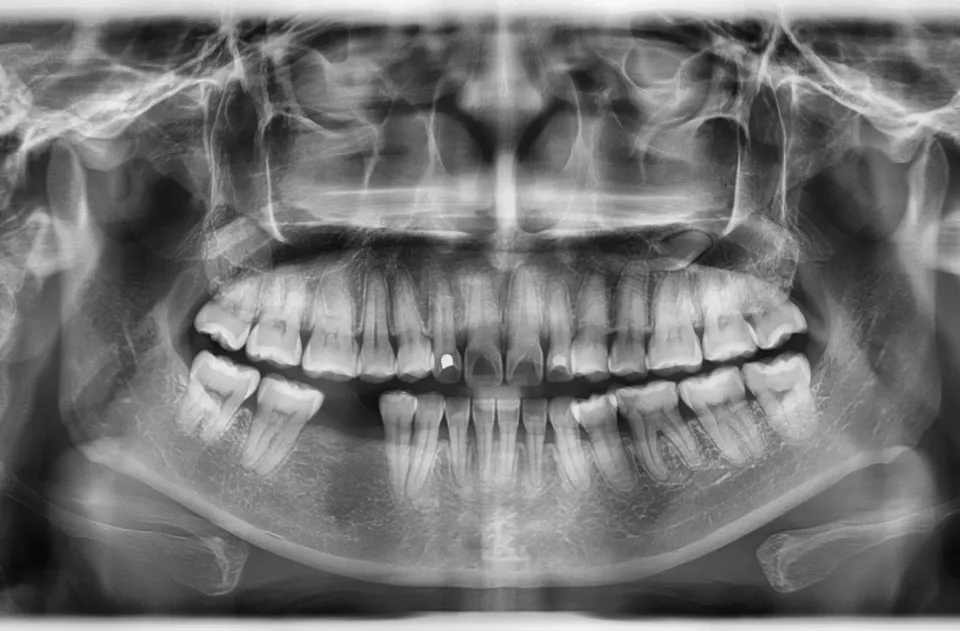

Your teeth do more than help you chew and speak; their roots play a vital role in maintaining jawbone density. Each time you bite or chew, the roots send gentle pressure through the bone, stimulating ongoing renewal.

When a tooth is lost, that stimulation stops. Without it, the surrounding bone begins to resorb, or shrink, as the body redirects minerals elsewhere. Over time, this can cause the jawbone to thin and the gum line to recede, altering facial contours and creating a prematurely aged appearance.

Dental implants replicate the structure of natural tooth roots. Each implant consists of a small titanium post surgically placed into the jawbone. Over the next few months, the bone grows and fuses around the post in a process called osseointegration.

This fusion allows the implant to function just like a natural root, delivering the same kind of mechanical stimulation needed to maintain bone density. As a result, implants effectively halt bone loss and help preserve the strength and volume of the jaw.